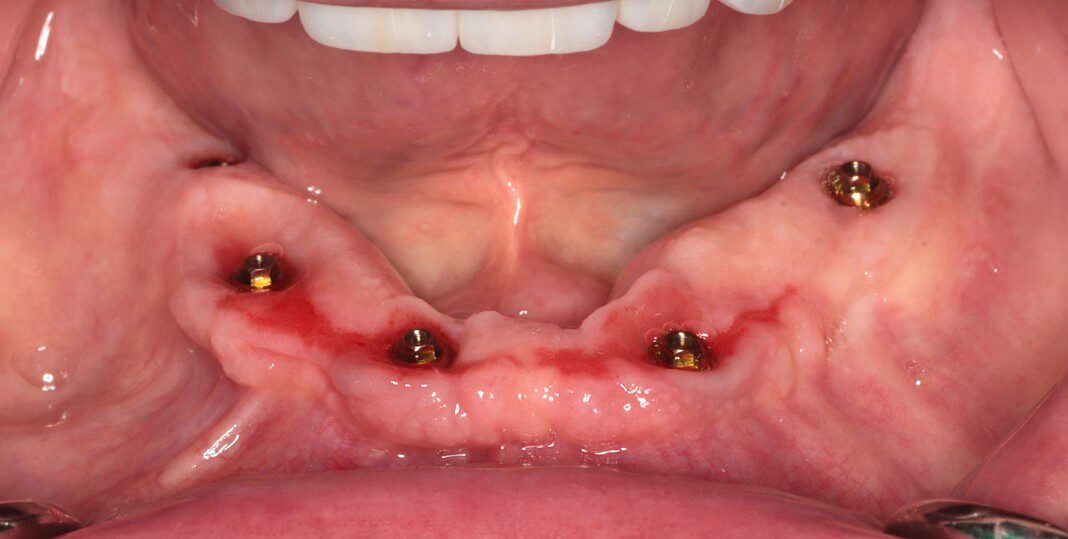

Three months post, first surgery the patient returns for implant uncovering and these are the impression copings preparing for the fixed temporary bridge.